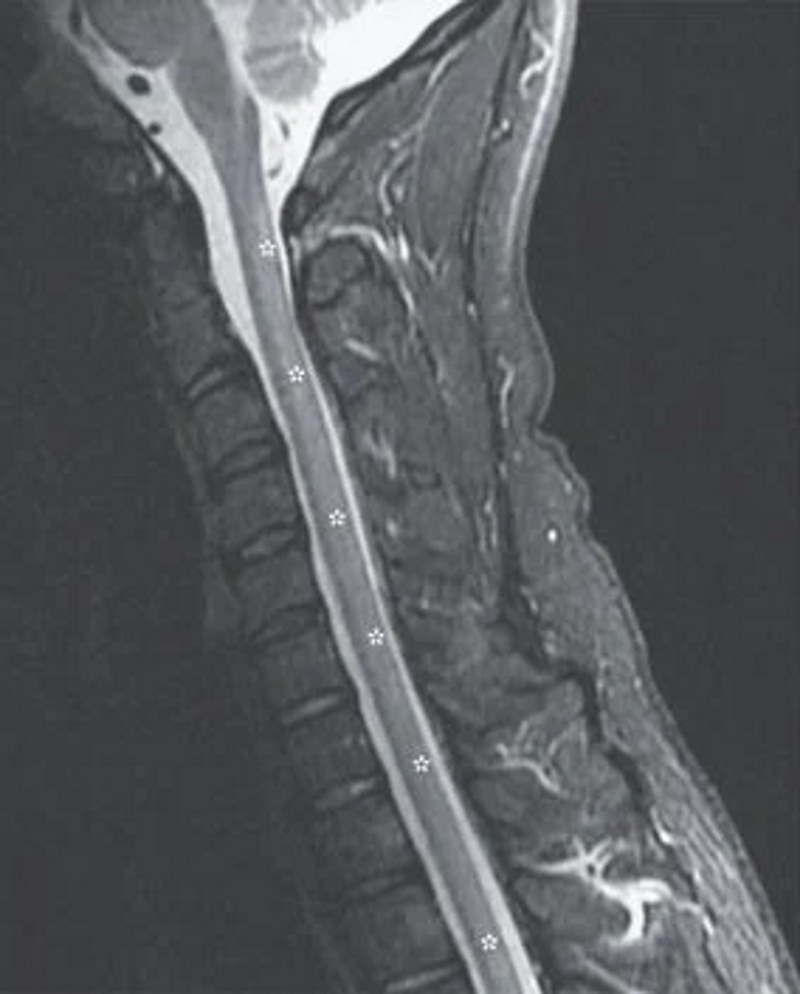

Badanie rezonansem magnetycznym wykazało, że u pacjenta rozwija się mielopatia, czyli ucisk na rdzeń kręgowy wywołany stanem zapalnym. Uszkodzenie i zwyrodnienie nerwów było spowodowane długotrwałym stosowaniem podtlenku azotu, które doprowadziło do niedoboru witaminy B12.